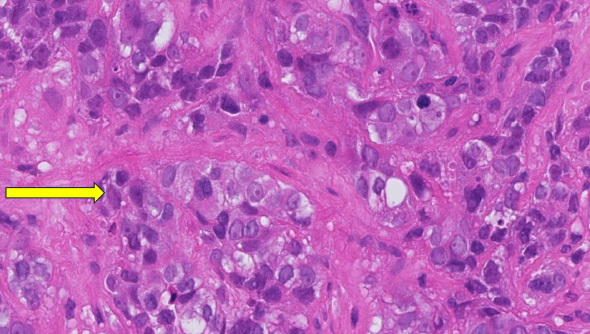

This is a patient where there are NO immune cells (No TILs, No Tumor Infiltrating Lymphocytes), so the immune system of the patient is not attacking the cancer (yellow arrow).

These patients don’t have a very good outcome, so chemotherapy is needed.

This analysis only needs a microscope and can be done by all laboratories globally.